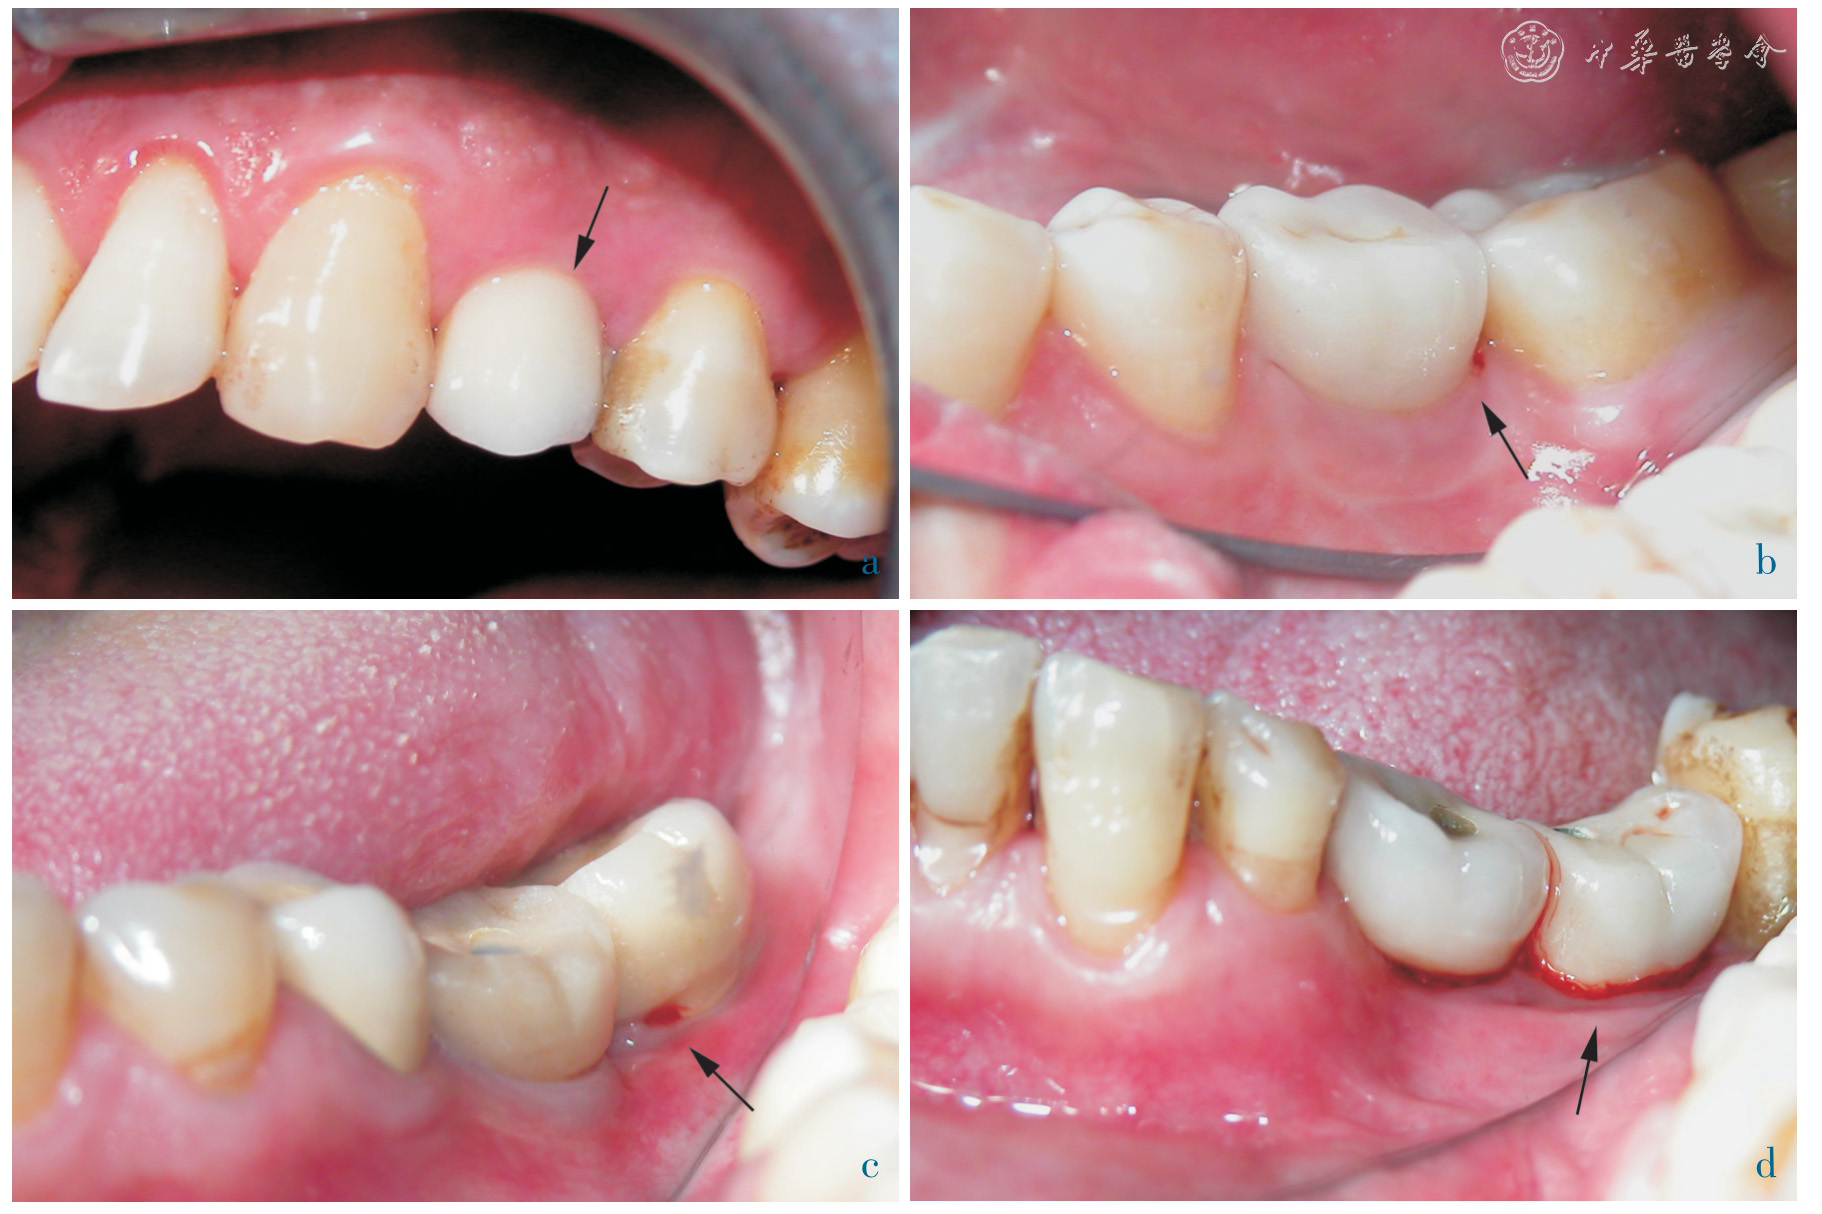

A total of 70 dental implants were placed in the posterior regions of 42 partially edentulous patients. 24 crowns were screw-retained, while 46 crowns were cementretained. Peri-implant marginal bone level, modified plaque index (mPLI), modified sulcus bleeding index (mSBI) and esthetic fulfillment were recorded at the 12 months recall after implant loading.

The mean peri-implant marginal bone lost in screw-retained group and cementretained group were 0.78 mm and 0.68 mm, respectively. The median values of mPLI and mSBI were both 1 in screw-retained group, and also 1 in cement-retained group. The median scores of esthetic fulfillment were both 1 in screw-retained and cement-retained group. The differences of marginal bone resorption, peri-implant soft tissue condition and patient satisfaction between two groups were statistically not significant (P >0.05).